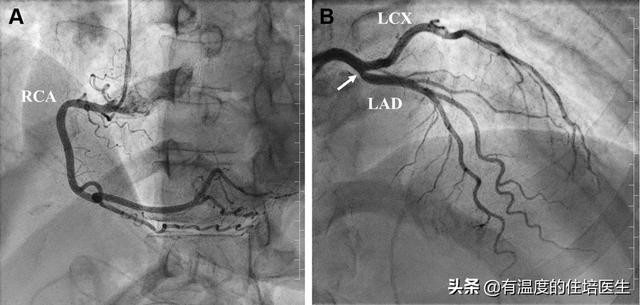

Les trois artères coronaires principales qui alimentent notre cœur en sang et en oxygène sont divisées par la très courte artère coronaire gauche.artère circonflexe gauche和artère descendante antérieure gaucheaussiartère coronaire droiteIngrédients.

Parmi eux.Les artères circonflexe et descendante antérieure gauches de l'artère coronaire gauche assurent les deux tiers de l'approvisionnement en sang de notre cœur.Le blocage de l'artère coronaire gauche est donc beaucoup plus grave que celui de l'artère coronaire droite !

Premièrement, l'approvisionnement en sang du cœur est principalement assuré par plusieurs gros vaisseaux sanguins de la branche descendante antérieure de l'artère coronaire gauche, de la branche circonflexe, de l'artère coronaire droite et de ses branches. Si ces grosses artères se bouchent, il y aura un déséquilibre entre l'apport sanguin et la consommation d'oxygène du cœur, et certaines manifestations cliniques se produiront. L'angine de poitrine peut être déterminée cliniquement s'il s'agit d'une douleur d'écrasement liée à l'activité dans la région précordiale, qui peut être soulagée après quelques minutes à dix minutes de repos, en particulier chez les patients présentant un nombre élevé de facteurs de risque cardiovasculaire tels que l'hypertension, le diabète sucré, l'hyperlipidémie, le tabagisme, etc.

Lorsque la sténose de la lumière de l'artère coronaire est inférieure à 25 %, il s'agit d'une sténose légère ; lorsque la sténose de la lumière est comprise entre 25 % et 49 %, il s'agit d'une sténose légère ; lorsque la sténose de la lumière est comprise entre 50 % et 69 %, il s'agit d'une sténose modérée ; lorsque la sténose de la lumière est comprise entre 70 % et 99 %, il s'agit d'une sténose sévère ; lorsque la sténose de la lumière est supérieure à 100 %, il s'agit d'une occlusion. Lorsque la sténose de la lumière coronaire dépasse 50 %, une maladie coronarienne est diagnostiquée et nécessite un traitement à vie à base de statines, de médicaments hypolipidémiants, d'aspirine et d'autres médicaments antiplaquettaires.

En fait, nous savons tous que la forme du cœur est similaire à un cône inversé, comme une tête de melon, et que les artères coronaires sont situées au sommet de la tête, entourant le cœur pendant une semaine, d'où son nom. L'artère coronaire gauche est divisée en deux branches, dont l'artère coronaire gauche est divisée en deux branches, la branche descendante antérieure gauche et la branche de gyration, réparties dans différentes régions du cœur.